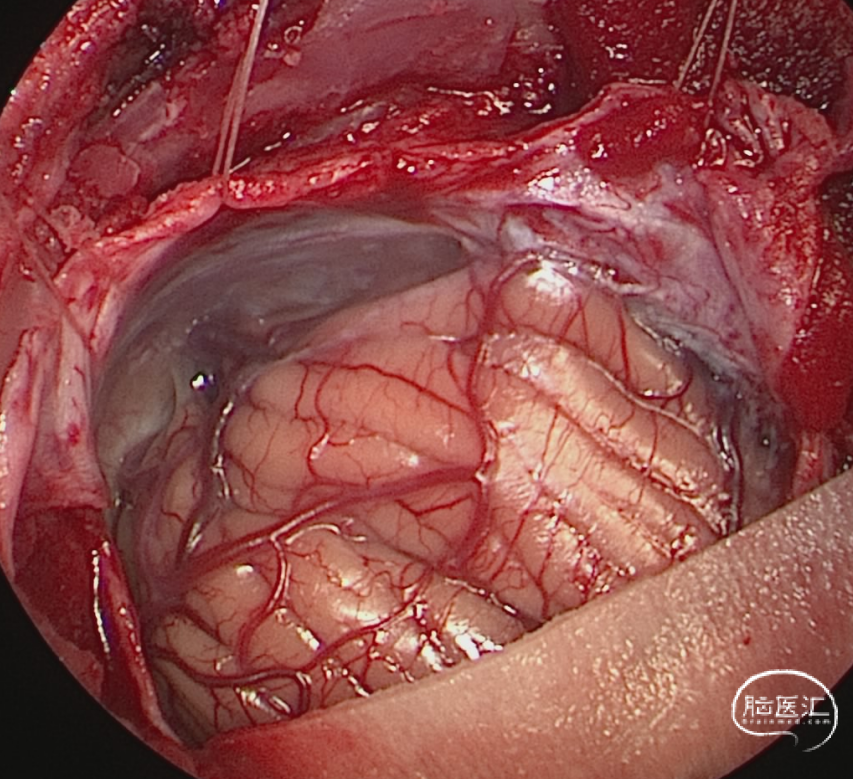

术中图片

熟悉图中解剖层次,理解肿瘤在松果体区/幕缘孔/鞍背的比邻结构,保护相关血管与神经(图片摘自:Sanai N, Mirzadeh Z, Lawton MT. Supracerebellar-supratrochlear and infratentorial-infratrochlear approaches: gravity-dependent variations of the lateral approach over the cerebellum. Neurosurgery. 2010;66(6 Suppl Operative):264-274. doi:10.1227/01.NEU.0000369653.12185.FD)